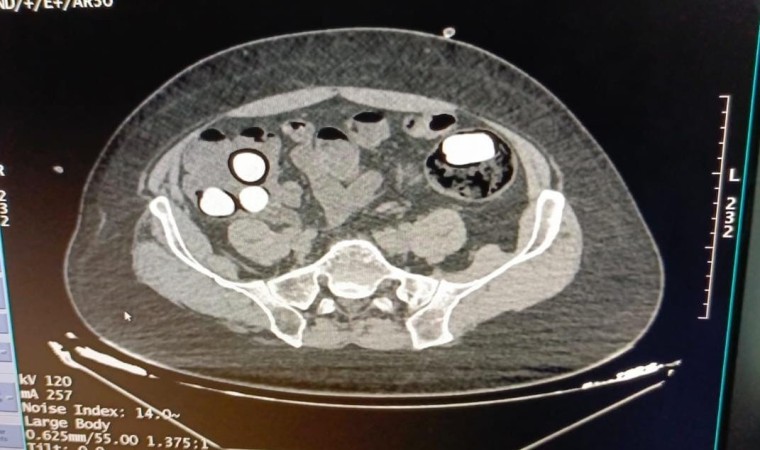

Kırşehir İl Emniyet Müdürlüğü Narkotik Suçlarla Mücadele Şube Müdürlüğü ekipleri tarafından yapılan çalışmalarda yabancı uyruklu Y.S. ve H.S.’nin doğu illerinden ülkeye kaçak yollarla girdikleri ve batı illerine uyuşturucu madde kuryeliği yaptıkları tespit edildi. Takibe alınan uyuşturucu kuryelerinin seyahat ettiği yolcu otobüsü Kırşehir’de durduruldu. Gözaltına alınan ve hastaneye götürülen şahısların midelerinde kapsül bulunduğu tespit edildi. Şahısların midelerinde zulaladığı 126 kapsül halinde 1 kilo 300 gram ve 44 kapsül halinde 550 gram uyuşturucu madde ele geçirildi.